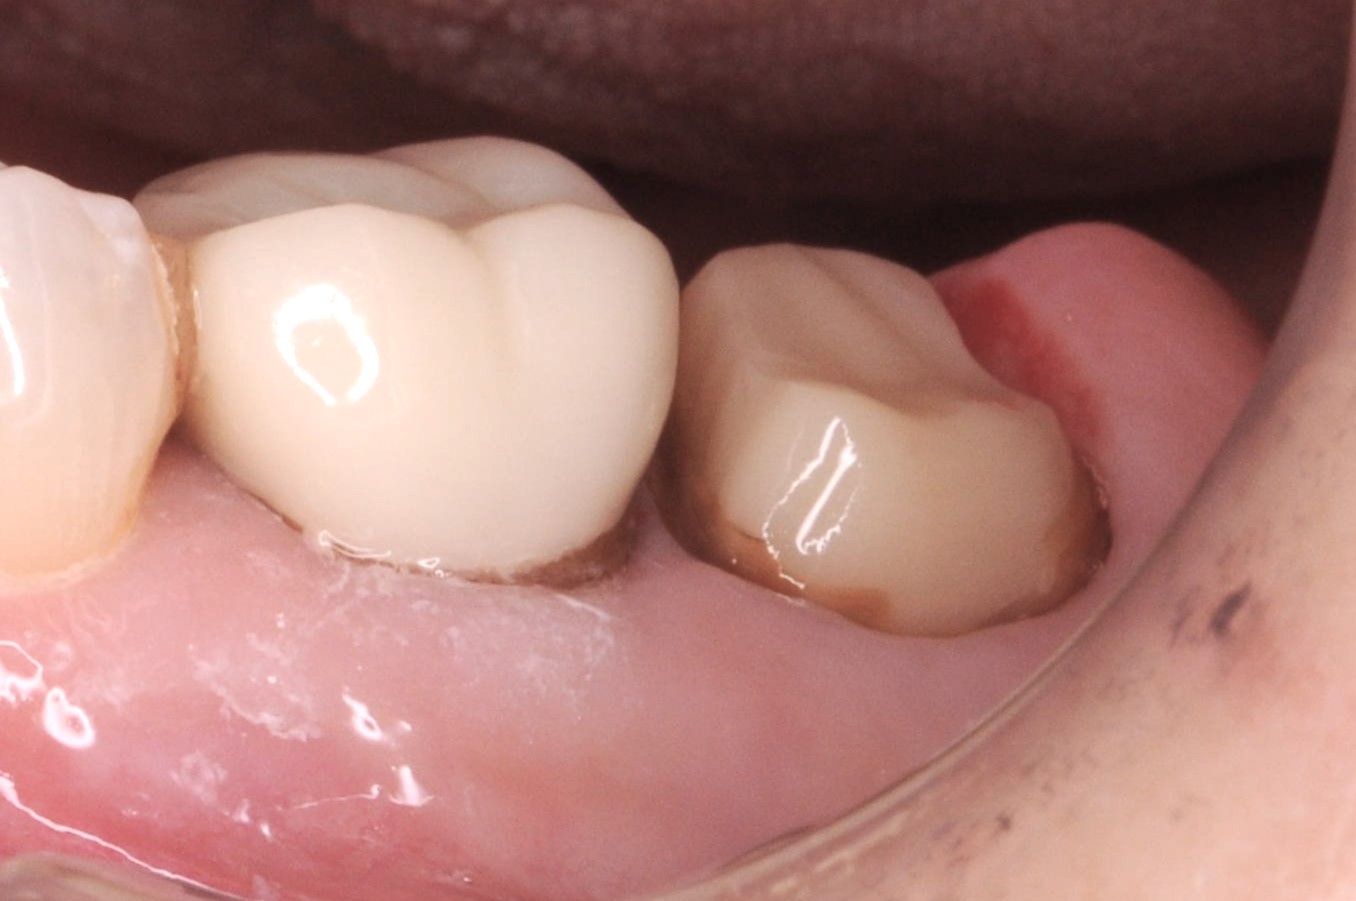

右上7精密根管治療~セラミックス補綴

噛んだ時の違和感を訴えられ、以前のセラミックスクラウンを除去し根管治療開始。 ラバーダム下での2回の根管治療を経て、根管充填と支台築造を行った状態から、精密なクラウン用の形成と印象を行い、セラミックスクラウンの装着。 奥から2番目の他院のセラミックスは縁取りが歯と合っておらず、また、表面…